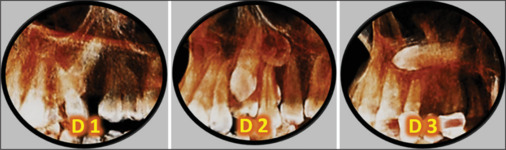

Results: For the total sample, forty patients (40) had impacted canines with a mean age of 22.6 years. Female to male ratio was 1.5:1. The maxilla represented 80.6% of total impaction cases. Palatally impacted canines represented 72.6% and were mostly seen bilaterally. The mandible formed 19.4% of impacted canines. Mesially and vertically angulated impacted teeth represented the majority of the cases for upper and lower jaws respectively. The impaction depth was recognized as D2 at the maxilla and D1 at the mandible as the commonest impaction level. Apical mislocation was presented in 21% of cases.